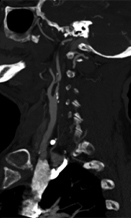

A CT angiogram is ordered for the patient. Results are shown in Figure 3.

Figure 3. The patient’s CT angiography scan showing (A) intracranial axial view and (B) right carotid sagittal view.

The patient’s CT angiography scan shows she suffered abrupt cessation of blood flow due to occlusion of the right internal carotid artery terminus and right middle cerebral artery but maintained some distal cerebral collateral flow (Figure 4A). The likely etiology of the patient’s occlusion is symptomatic carotid atheroemboli from severely stenotic proximal right cervical internal carotid artery (Figure 4B), and recanalization should be considered for secondary stroke prevention moving forward. (Further discussion of this is beyond the scope of this case.)

A.

Figure 4. Patient’s CT angiography scan (from Figure 3). Figure 4A shows abrupt cessation of blood flow caused by the occlusion of the right internal carotid artery terminus and right middle cerebral artery (solid yellow arrow) while maintaining some distal cerebral collateral flow (white arrows). On Figure 4B, the open yellow arrow points to the symptomatic carotid atheroemboli from severely stenotic proximal right cervical internal carotid artery.